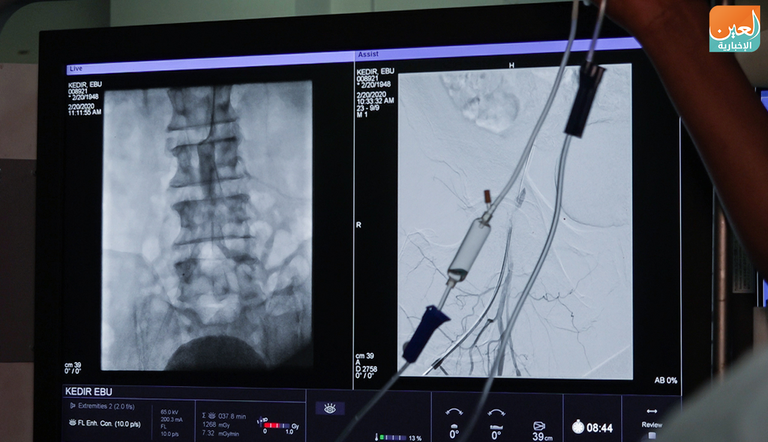

وتابعت كاميرا "العين الإخبارية" مراحل عملية جراحية أجراها الوفد بقيادة الدكتور أيمن إسكندر، في مستشفى "طقور أنبيسا"، تمت بنجاح، وكان في الماضي من الصعب إجراء هذا النوع المعقد من العملية داخل البلاد.

وقال إسكندر إنهم تمكنوا من علاج مرضى كانوا يعانون من آلام في أرجلهم، ويواجهون صعوبة في الحركة لإصابتهم بانسداد في الشرايين.